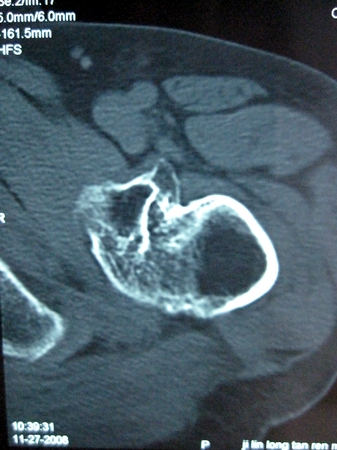

以下是引用lkc8963在2008-12-19 21:19:00的发言:[br]左?右?患侧大转子上移,股骨颈骨质浓杂,髋周见多发条片状骨化影,以小转子为著,多为陈旧性股骨颈骨折后改变并骨化性肌炎.请咨询既往史!